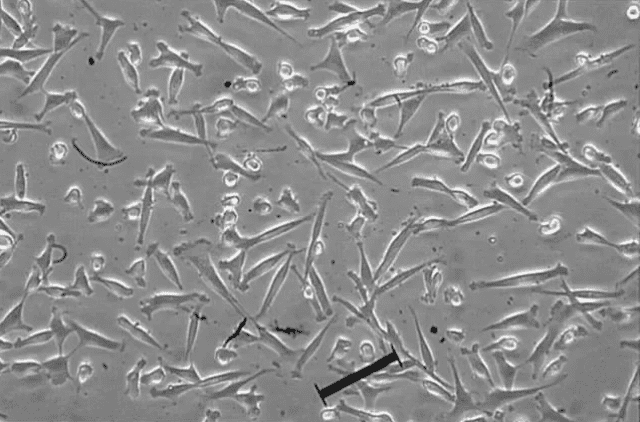

間充質干細胞(mesenchymal stem cells,MSC)是干細胞的一種,因能分化為間質組織而得名,具有亞全能分化潛能,在特定的體內外環境下,能夠誘導分化成為多種組織細胞。間充質干細胞具有干細胞的共性,即自我更新、多向分化和歸巢的能力。

具有很強的增殖能力和多向分化潛能,在體內外合適的環境中能夠分化為肌細胞、肝細胞、成骨細胞、脂肪細胞、軟骨細胞、基質細胞等細胞。

具有來源方便、易于分離、培養、擴增和純化的優點,經多次傳代和擴增后仍具有干細胞的特性,不具有免疫排斥的特性。